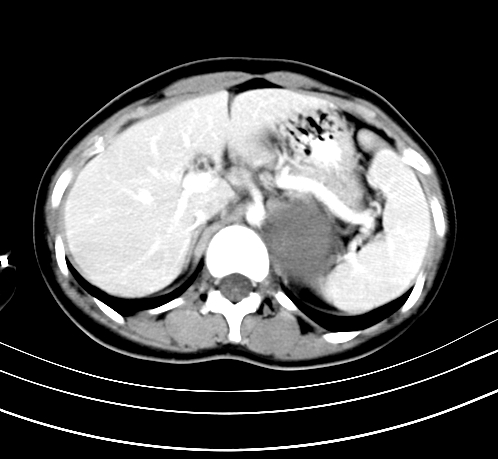

动脉期